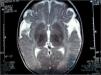

Se realiza una primera resonancia magnética (RM) cerebral a las 48h, que se repite a los 7 días de evolución, en las cuales no se aprecian lesiones parenquimatosas, ni áreas de edema ni de hemorragia (fig. 2).